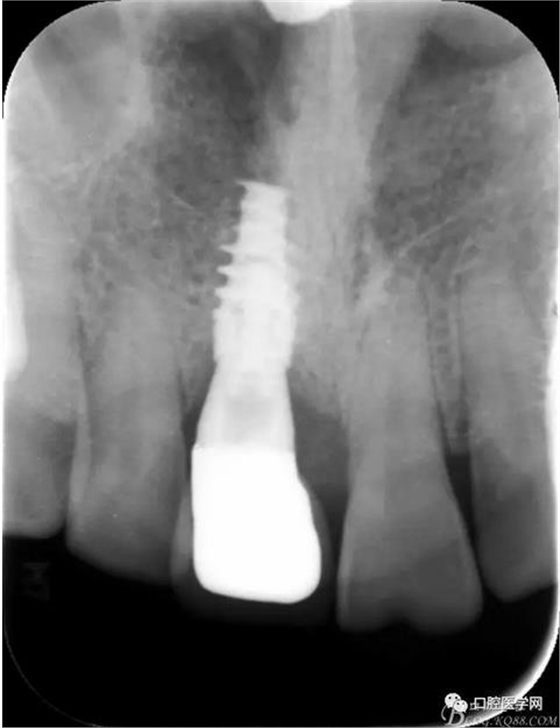

圖3 術后CT

圖24 術后 X光片